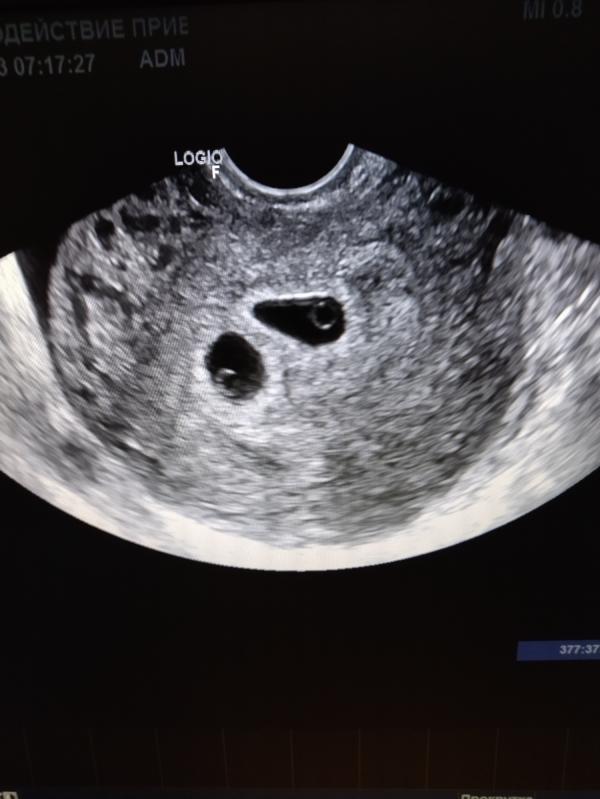

УЗИ на 22 дпп: двойня?

Пополню ленту хорошими новостями 🙂 22 дпп УЗИ, наши две пуговки😍🥰 сб есть, по узи срок 5недель и 5 дней, по месячным 6 и 1. Оставляю для истории фото малышей